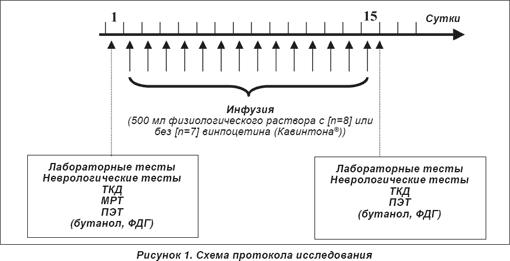

Точный протокол исследования представлен на рисунке 1. Все субъекты получали внутривенные инфузии 500 мл физиологического раствора (Salsol) длительностью 45 минут ежедневно на протяжении 14 суток. В первой подгруппе (8 пациентов — «группа плацебо») винпоцетин (Кавинтон®) в раствор для инфузии не добавлялся, в другой (7 пациентов — «группа активной терапии») субъекты исследования получали препарат (Кавинтон®, Гедеон Рихтер, Будапешт) в инфузии из расчета 1 мг/кг массы тела.